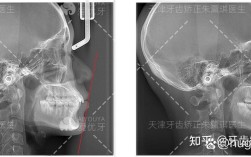

| 初诊检查 | 医生进行口腔检查、取研究模型、拍摄X光片(全景片、头颅侧位片、CBCT等),分析牙齿、颌骨、面部软组织情况。 |